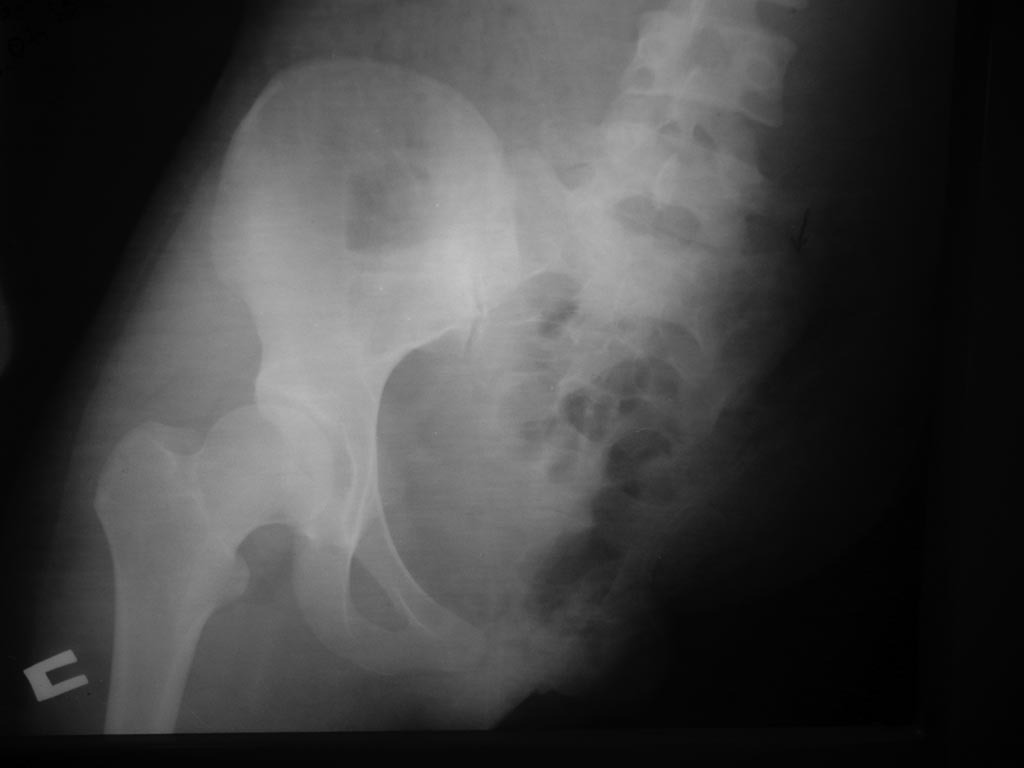

Уважаемые коллеги, возможно ли протезирование при травматическом отрыве

левой половины таза и нижней конечности.

Больная К. 20 лет Ds: Тяжёлая сочетанная травма в ДТП. Травматический

отрыв левой половины таза и левой нижней конечности. Обширная

размозжённая рана передней брюшной стенки слева, таза и ягодичной

области слева с обширным дефектом мышц передней брюшной стенки.

Уважаемые коллеги, возможно ли в дальнейшем протезирование данной

больной и где?